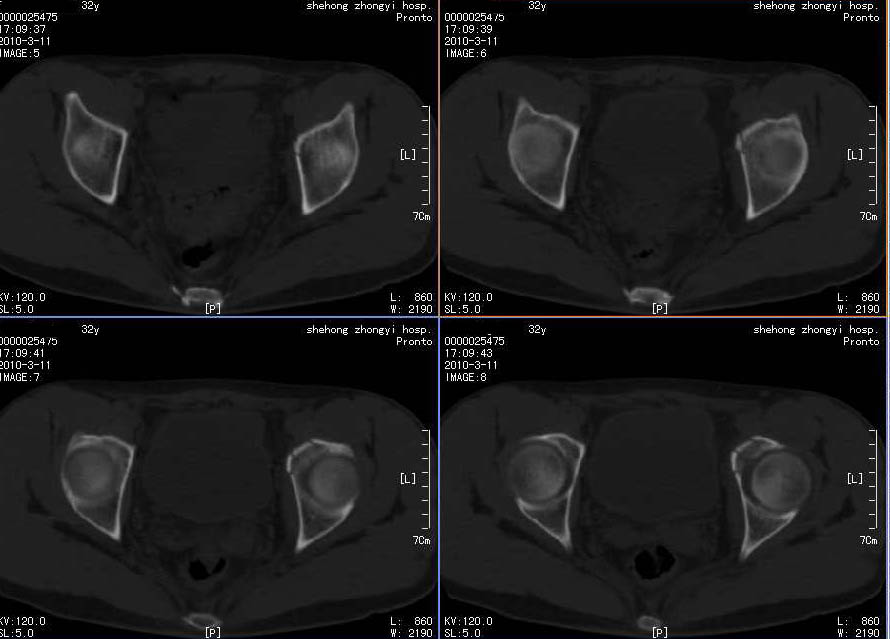

标题: x7022的CT结果髋臼骨折

因为病人症状较重,平片无问题,而ct有问题,所以影像检查应多方面结合,才能避免漏诊。

左侧髋臼可见一线形低密度影。